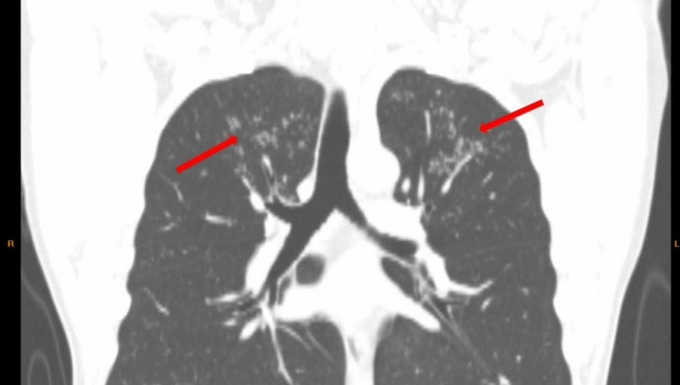

Ngày 6/12,BS.CK2 Cao Thị Hồng,Phó khoa Chăm sóc sức khỏe theo yêu cầu,phụ trách Trung tâm kiểm tra sức khỏe Chợ Rẫy Việt - Nhật (HECI),cho biết CT ngực liều thấp phát hiện có hình ảnh tổn thương ở thùy trên phổi. Tầm soát chuyên sâu về lao cho kết quả dương tính. Bệnh nhân được điều trị theo phác đồ bệnh lao khoảng 3 tháng nay,không còn triệu chứng ớn lạnh nhẹ về chiều.

Hình ảnh tổn thương dạng nụ trên cành ở thùy trên hai phổi bệnh nhân. Ảnh: Bệnh viện cung cấp